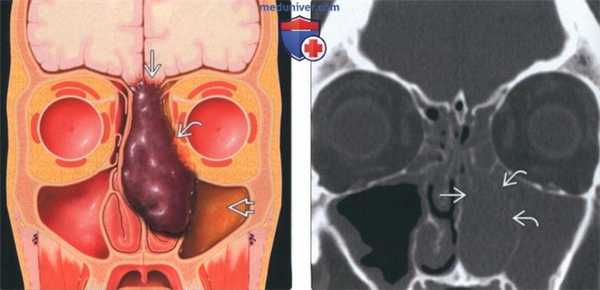

(Слева) На рисунке в корональной плоскости изображено темное, пигментированное (с высоким содержанием меланина) объемное образование в полости носа. Показаны признаки инвазии основания черепа, глазницы и наружной стенки полости носа. Носовая перегородка отклонена без признаков инвазии. В левой верхнечелюстной пазухе находится «запертый» секрет.

(Справа) На корональной КТ в костном окне у пациента с обструкцией носа слева и носовым кровотечением визуализируется объемное образование в полости носа слева, приводящее к эрозии средней носовой раковины слева и отдельных участков наружной стенки полости носа. Нарушена пневматизация верхнечелюстной пазухи и ячеек решетчатого лабиринта слева.